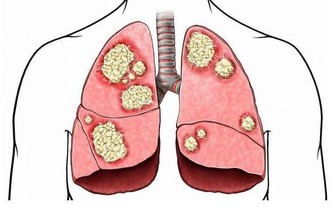

三、肺臟排毒

肺是最容易積存毒素的器官之一。因為人每天的呼吸會將約1000升空氣送入肺中,空氣中飄浮的許多細菌、病毒、粉塵等有害物質也隨之進入肺臟。當然,肺也能通過呼氣排出體內代謝的二氧化碳等廢氣和其他有害入侵者。

肺臟有毒素堆積,會使人經常感冒、咳嗽、哮喘,氣管敏感。中醫認為,肺臟和大腸是一套系統,互為表里。當肺臟有毒素時,腸道內也會有不正常淤積,出現便秘。

肺排毒的時間是凌晨3點到5點。肺臟功能最強的時間是早上7點到9點,此時最好能夠通過運動排毒。在肺功能最強的時候進行慢跑等有氧運動,能強健肺排出毒素的功能。

【排毒措施】

1、堅持有氧運動能增強心肺功能,促進周身血液循環,增強氧氣輸送和排出毒素的作用。

2、肺主皮毛,管理皮膚,所以痛痛快快地出一身汗,讓汗液帶走體內的毒素,會讓我們的肺清爽起來。

3、在空氣清新的地方經常練習深呼吸,可以減少體內廢氣的殘留。主動咳嗽也可幫助肺臟排毒。

4、多吃百合、蓮子,可潤肺清心。

5、黑木耳、白木耳、海帶等含有豐富的植物膠質,有較強的吸附力,可以清肺、清潔血液,常食用可以有效清除體內垃圾毒素。